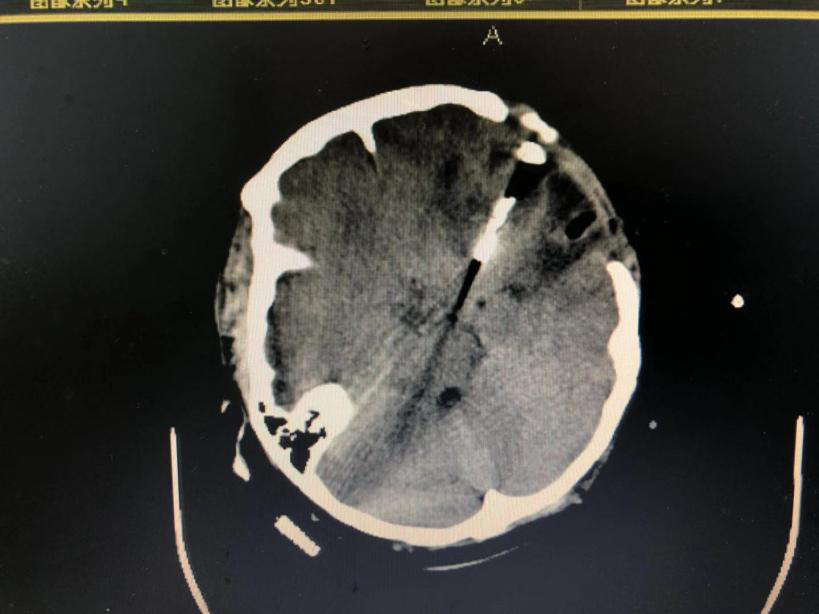

病例一:患者女性,49岁,因突发意识不清2小时,伴喷射性呕吐,大汗、四肢抽搐,就诊于本院神经外科接受治疗。积极完善相关检查,患者处浅昏迷,格拉斯评分7分,CT示:左侧额颞叶脑出血,量约33ml,并急诊行CTA(血管造影)示:左侧大脑中动脉M2段动脉瘤。急诊行“颅内血肿清除术+颅内动脉瘤夹闭+去骨瓣减压”,手术顺利,目前患者治愈出院。